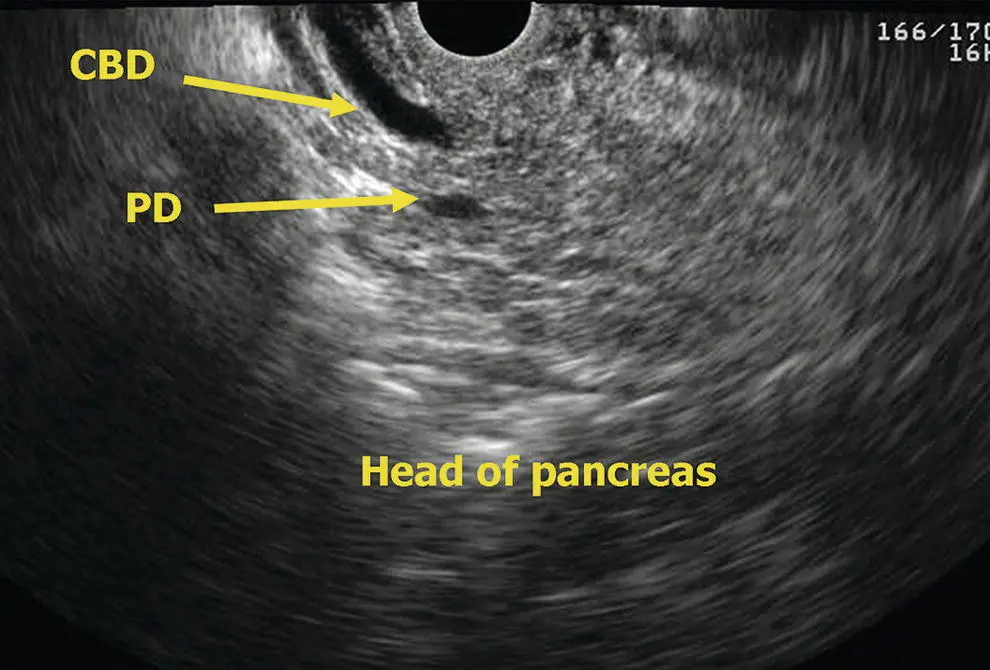

Figure 6.14 Linear EUS: head of pancreas. CBD, common bile duct; PD, pancreatic duct.